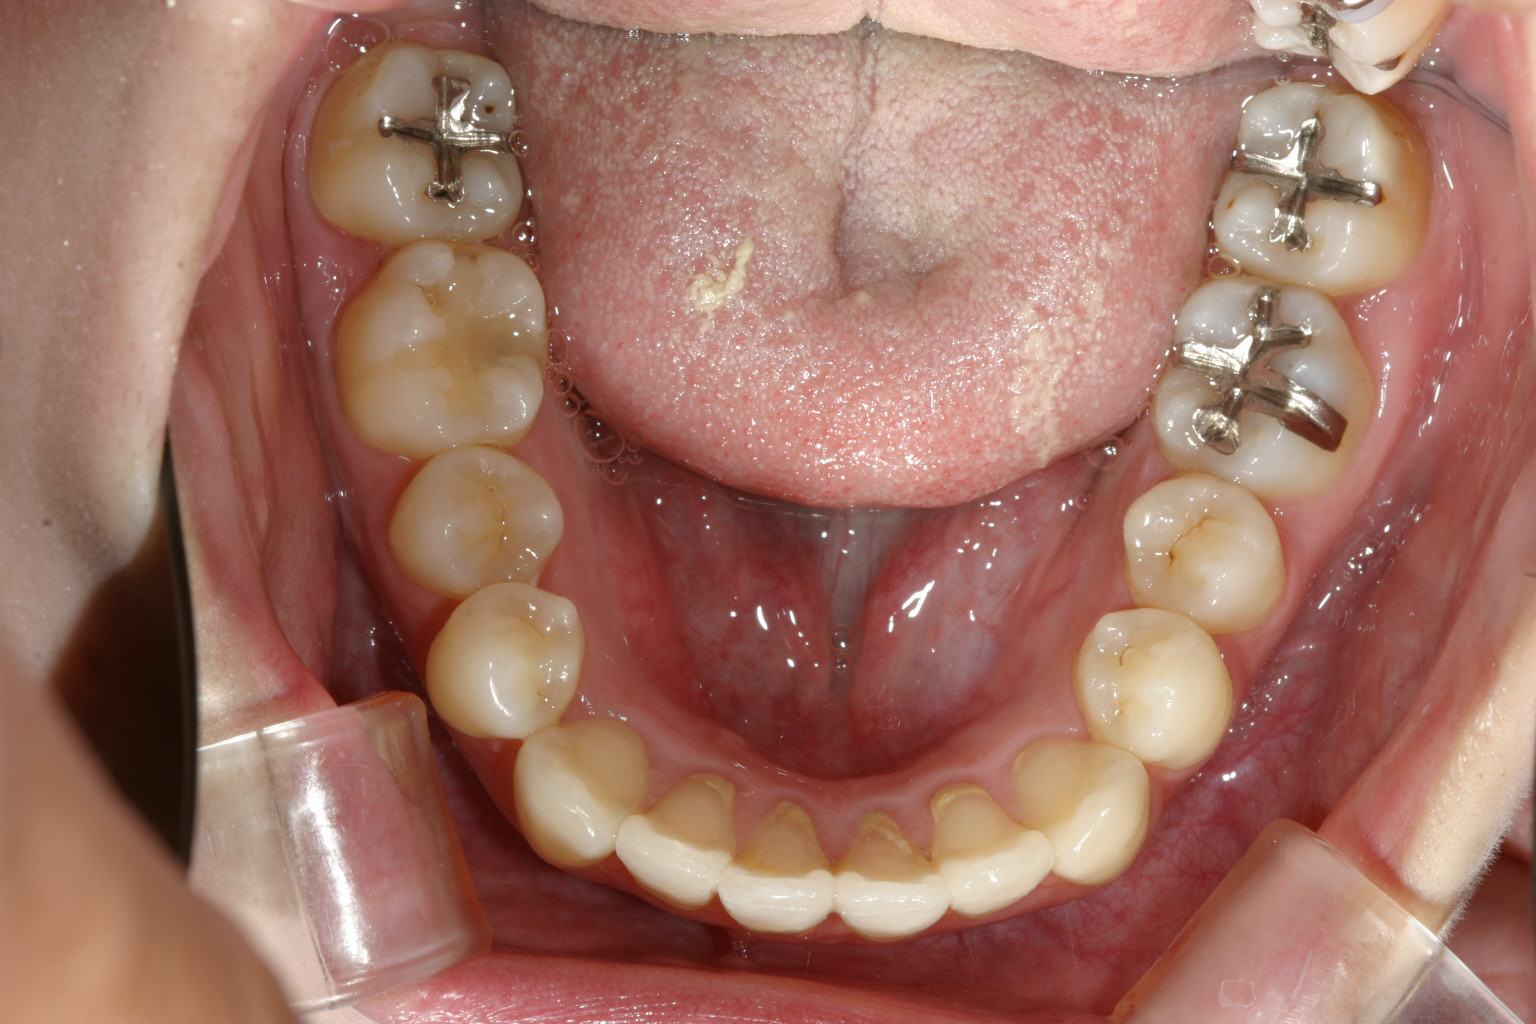

下顎も上と同じように調整しました。

綺麗なオーバージェットに改善しました。

今回のケースは上下額ともアーチがV字の為U字に出来たガチャガチャを改善しIPRを行い矯正しました。

大抵の場合アーチ形状の修正とIPRを行えば抜歯を行うことなく終えることが出来ます。